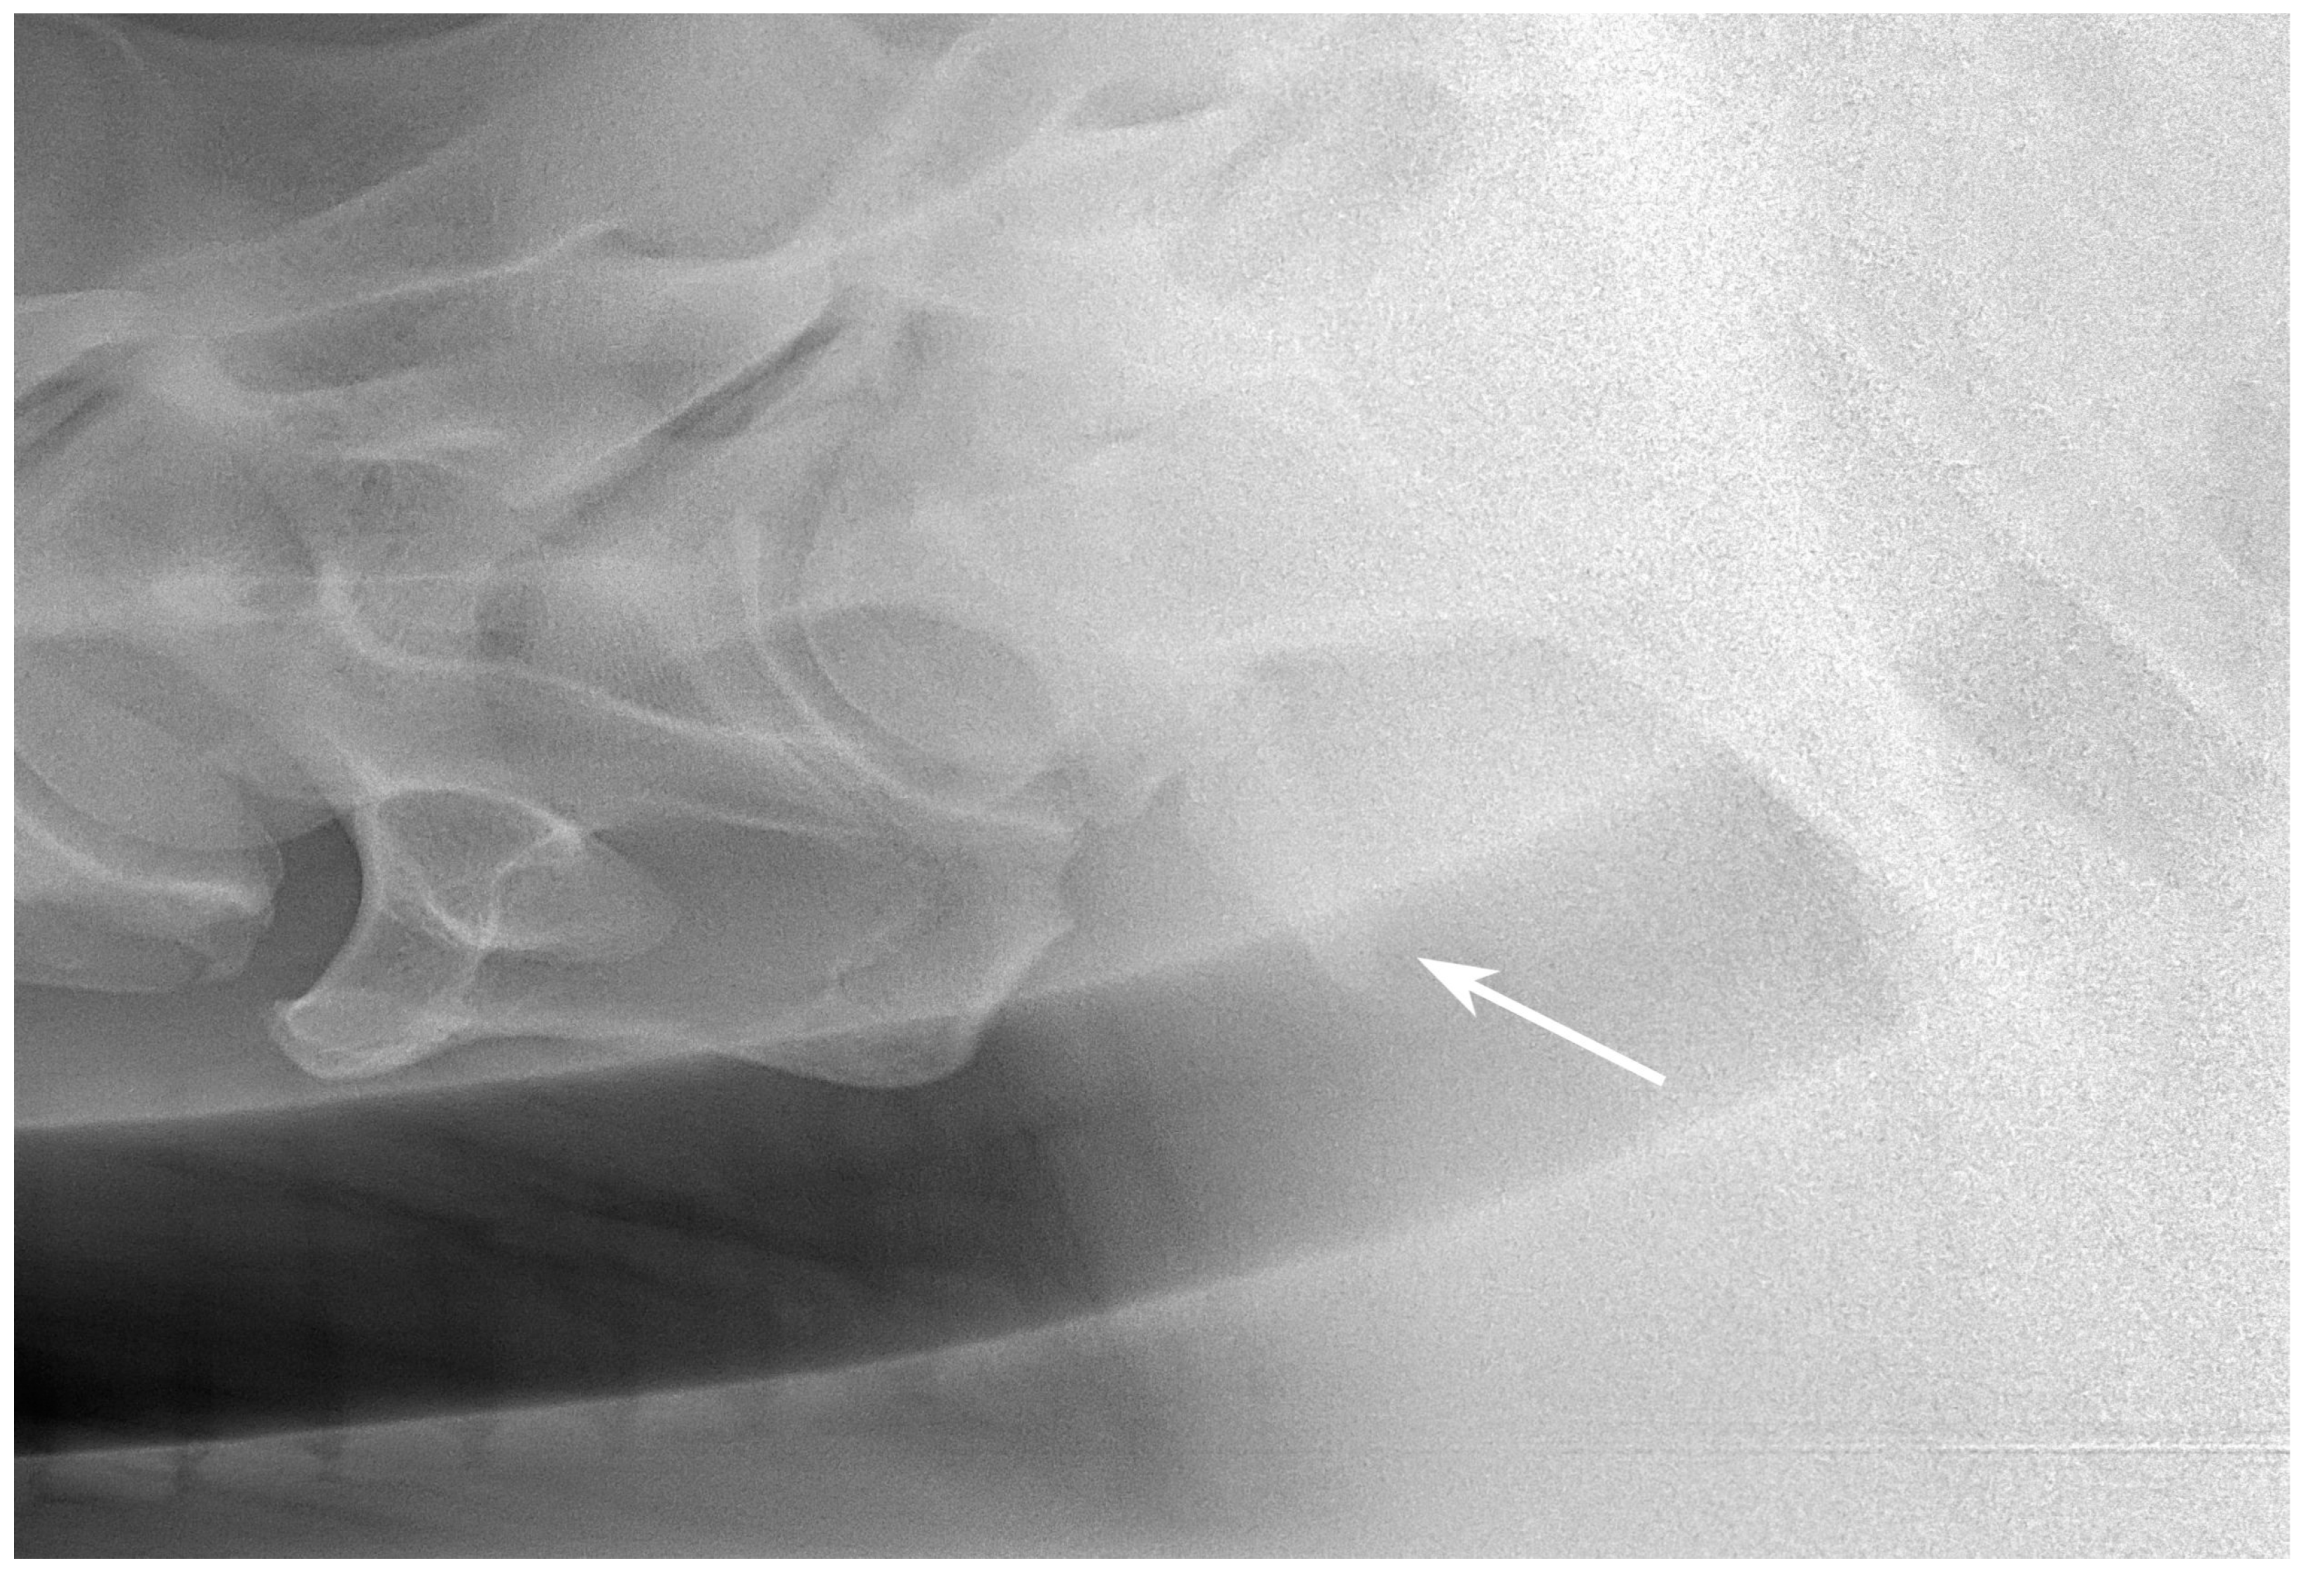

2.3. Radiographic Method

2.4. Classification System